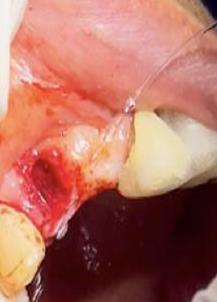

Figura 7. Exodoncia de la unidad dental, revisión del alveolo, curetaje y retiro de exudado purulento con cucharilla de lucas.

Elaboración: Los autores.